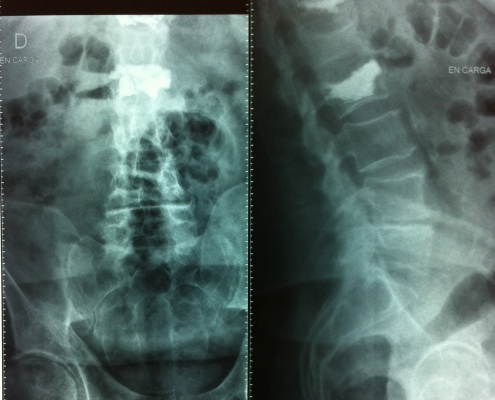

Puedes ver imágenes de una fractura y de la técnica quirúrgica de un caso real del 2015 tras este texto.